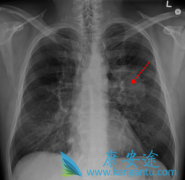

咳血是最为常见的肺癌早期症状

身体出现不适症状,去医院检查,然后查出某某病,这是多数人的看病思维套路。没错,很多疾病可能会出现某些不舒服的 肺癌早期症状 ,肺癌也不例外。癌症其实不可怕,可怕的是一发现就是晚期,所以早发现早诊断是关鍵,如何早期发现肺癌呢?大家最先想到 ...